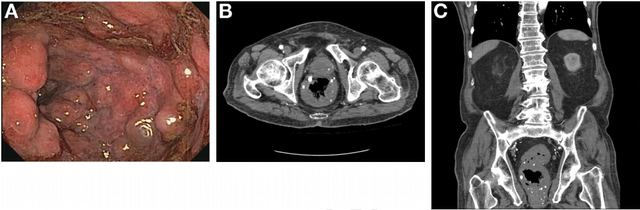

结肠镜检时发现从肛缘至直肠有一段长达10cm的紫色炎性病灶伴活动性出血(见图A),用双极探头进行治疗。该处病理活检结果为正常。腹部和盆腔CT显示乙状结肠直肠肠壁的同心性增厚和结肠壁钙化灶(见图B、C)。

CT检查的特征性表现是直肠同心性弥漫性增厚伴静脉石生成。如果CT下未见静脉石,MRI也可以协助诊断,且MRI能够更精确地评估肛门括约肌和周围结构的受累情况,从而指导治疗。